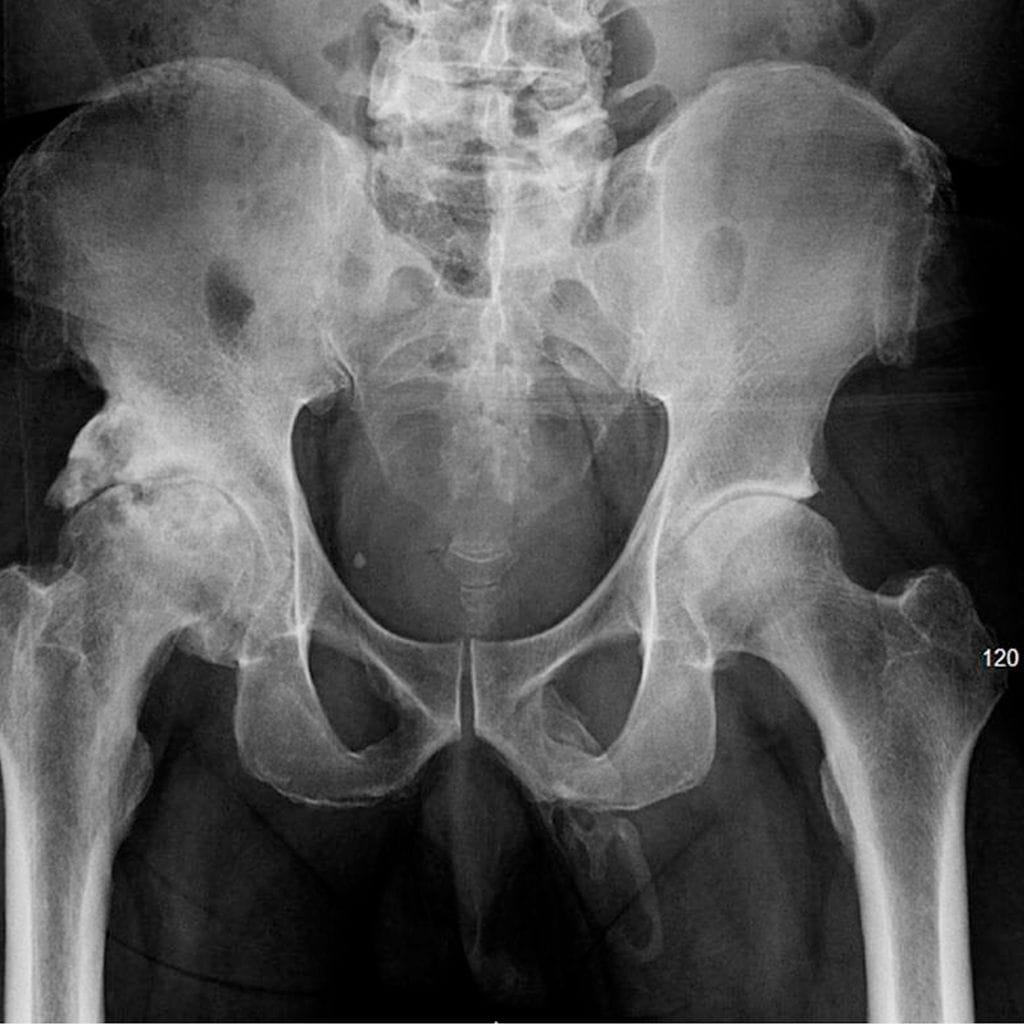

Nimettömäksi jäävä 63-vuotias mies vieraili newyorkilaisessa sairaalakeskuksessa kaaduttuaan ja loukattuaan polvensa. Koska mies oli alun perin kaatunut takapuolelleen, lääkärit ottivat röntgenkuvat potilaan lantion alueelta. Kuvaus paljasti jotain hyvin epätavallista.

Miehen peniksessä havaittiin plakkimaista kalkkeutumista. Lääkärit huomasivat siittimen alkaneen luutua koko vartensa mitalta, Urology Case Reports -julkaisussa ilmestyneessä tapausraportissa kerrotaan.